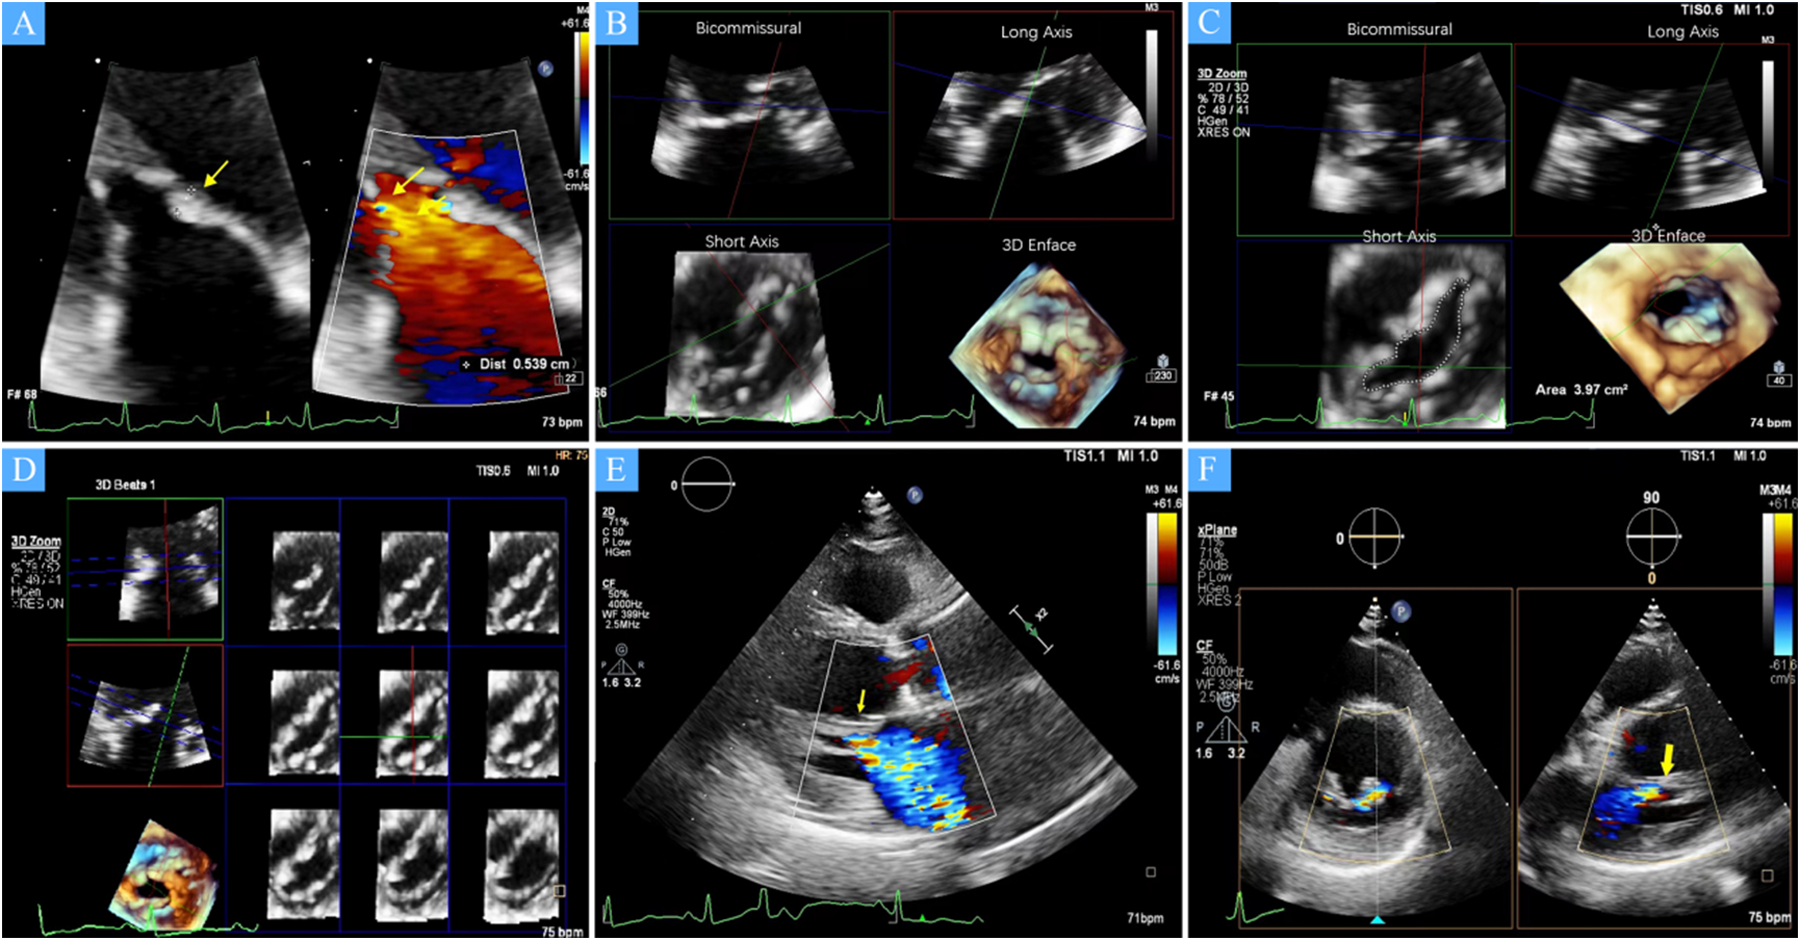

Figure 1

(A) A zoomed image of the mitral valve shows the thickness of the anterior leaflet in this area is approximately 5 mm (yellow arrow), with short, thick, and poorly differentiated chordae that directly connect the papillary muscles to the anterior leaflet, and narrow spaces between the abnormal chordae (yellow star). (B) Multiview 3D transthoracic echocardiography (3D TTE) illustrates short, thick, and poorly differentiated chordae with direct connection to the anterior leaflet. (C) Multiview 3D TTE reveals a mitral valve area of 3.97 cm2 without commissural fusion, effectively ruling out rheumatic valve disease. (D) Multislice 3D TTE shows uneven thickening of the mitral valve without commissural fusion and calcification. (E) The left ventricular long-axis view on transthoracic echocardiography (TTE) demonstrates a direct connection between the papillary muscle and the anterior mitral leaflet, with significant mitral regurgitation during systole (arrow). (F) TTE biplane short-axis view of the left ventricle shows a direct connection between the papillary muscle and the anterior mitral leaflet (yellow arrow).

The study cohort consisted of four patients, two males and two females, with a mean age of 68 (54–76) years. All patients were in NYHA functional class III–IV at baseline. Echocardiographic assessment showed complex mitral valve anatomy, with thickened and shortened chordae tendineae and superiorly displaced hypertrophied papillary muscles (Figure 1). The left ventricular end-diastolic diameter (LVEDD) was 60.5 (57–72) mm, and the left ventricular EF was 36.5 (32–47)%, with further echocardiographic and volumetric details provided in Tables 1–3.